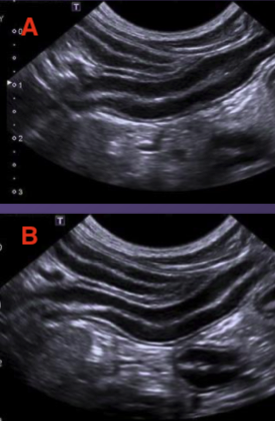

For the images belown state which one was imaged at a higher frequency:

B- sharper image